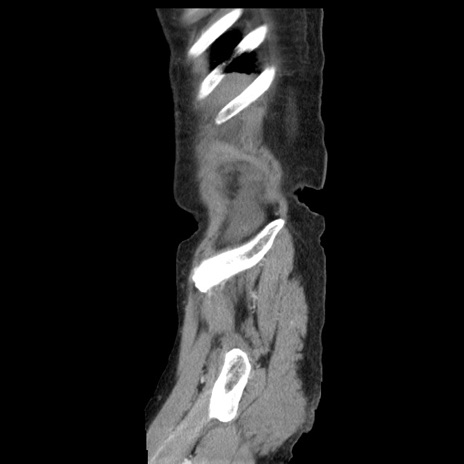

横断像

【症例】80歳代女性

【主訴】腹痛

【現病歴】8時間前から腹痛あり来院。

【既往歴】糖尿病、脂質異常症、子宮体癌にて子宮全摘術

【身体所見】意識清明・会話良好だが腹痛で苦悶様、全腹部にわたって反跳痛と圧痛あり

【データ】WBC 13600、CRP 0.14、LDH 224、CK 90